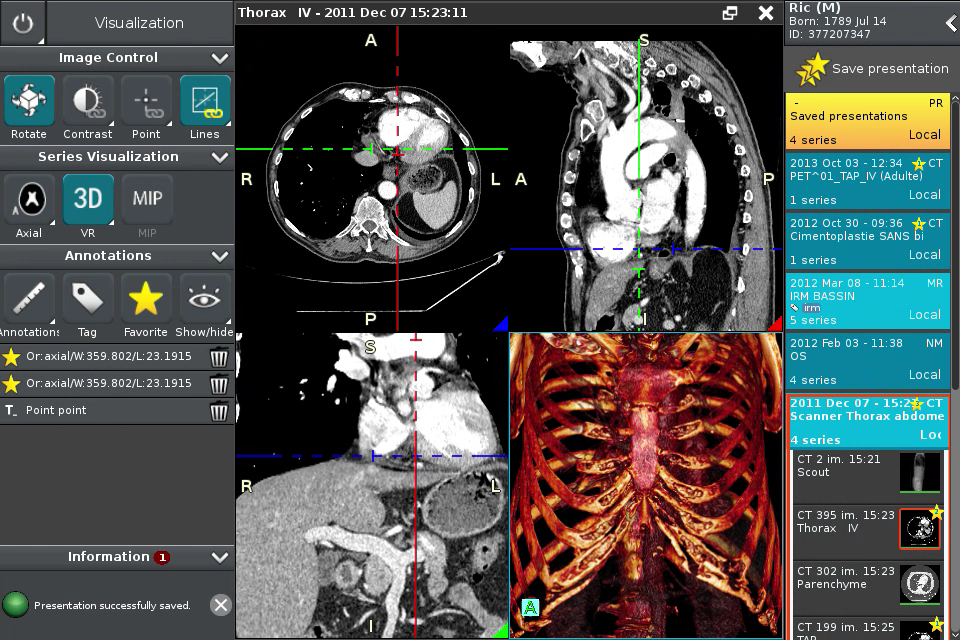

Anywhere Streaming is a DICOM visualization client that connects to Anywhere Server. It provide standard medical image navigation tools surch as : slicing, windowing, MPR, 3D VR, MIP, oblique ...

All standard medical image modalities are supported : MR, RX, CT, PET, NM, MG, US ...

Screenshots